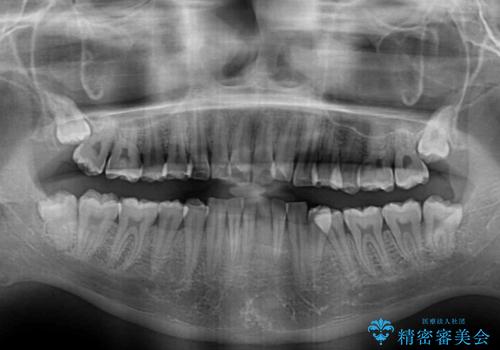

- 上下前歯のデコボコと、それに伴う出っ歯を気にして来院された患者様です。

インビザラインによる上下歯列の側方拡大と後方移動、IPR(歯と歯の間を削る)にるスペースの獲得により歯列を整えることとしました。

歯と歯の間を削ることでうまくスペースコントロールでき、また、毎日22時間以上しっかりとマウスピースを装着していただいたので、スムーズに治療が進みました。